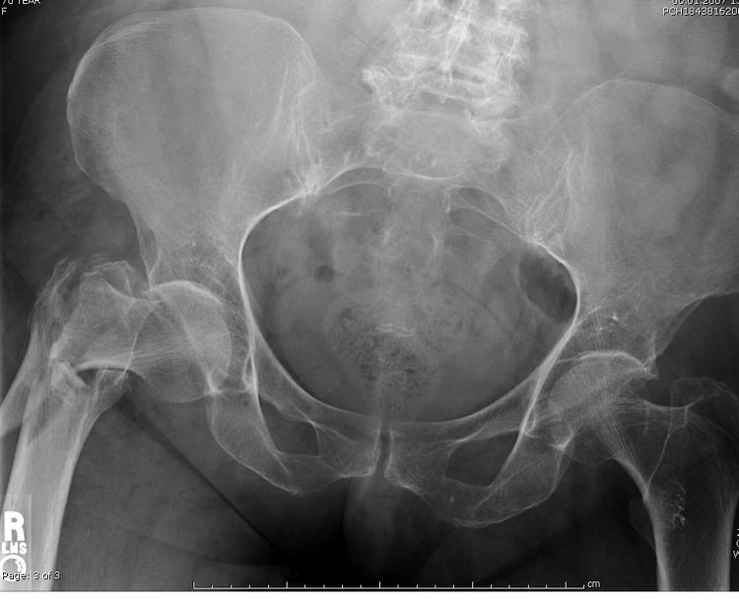

Здесь 83 года, травма в результате падения

судя по картинкам с ЭОПа явно использовались приемы непрямой репозиции под его контролем, а так же интраоперационный ЭОП-контроль положения винтов, без такого контроля операция может ухудшить ситуацию (опять же учтите сроки) т.к. результат буде зависеть в большей степени от искусства хирурга, а не от технологии